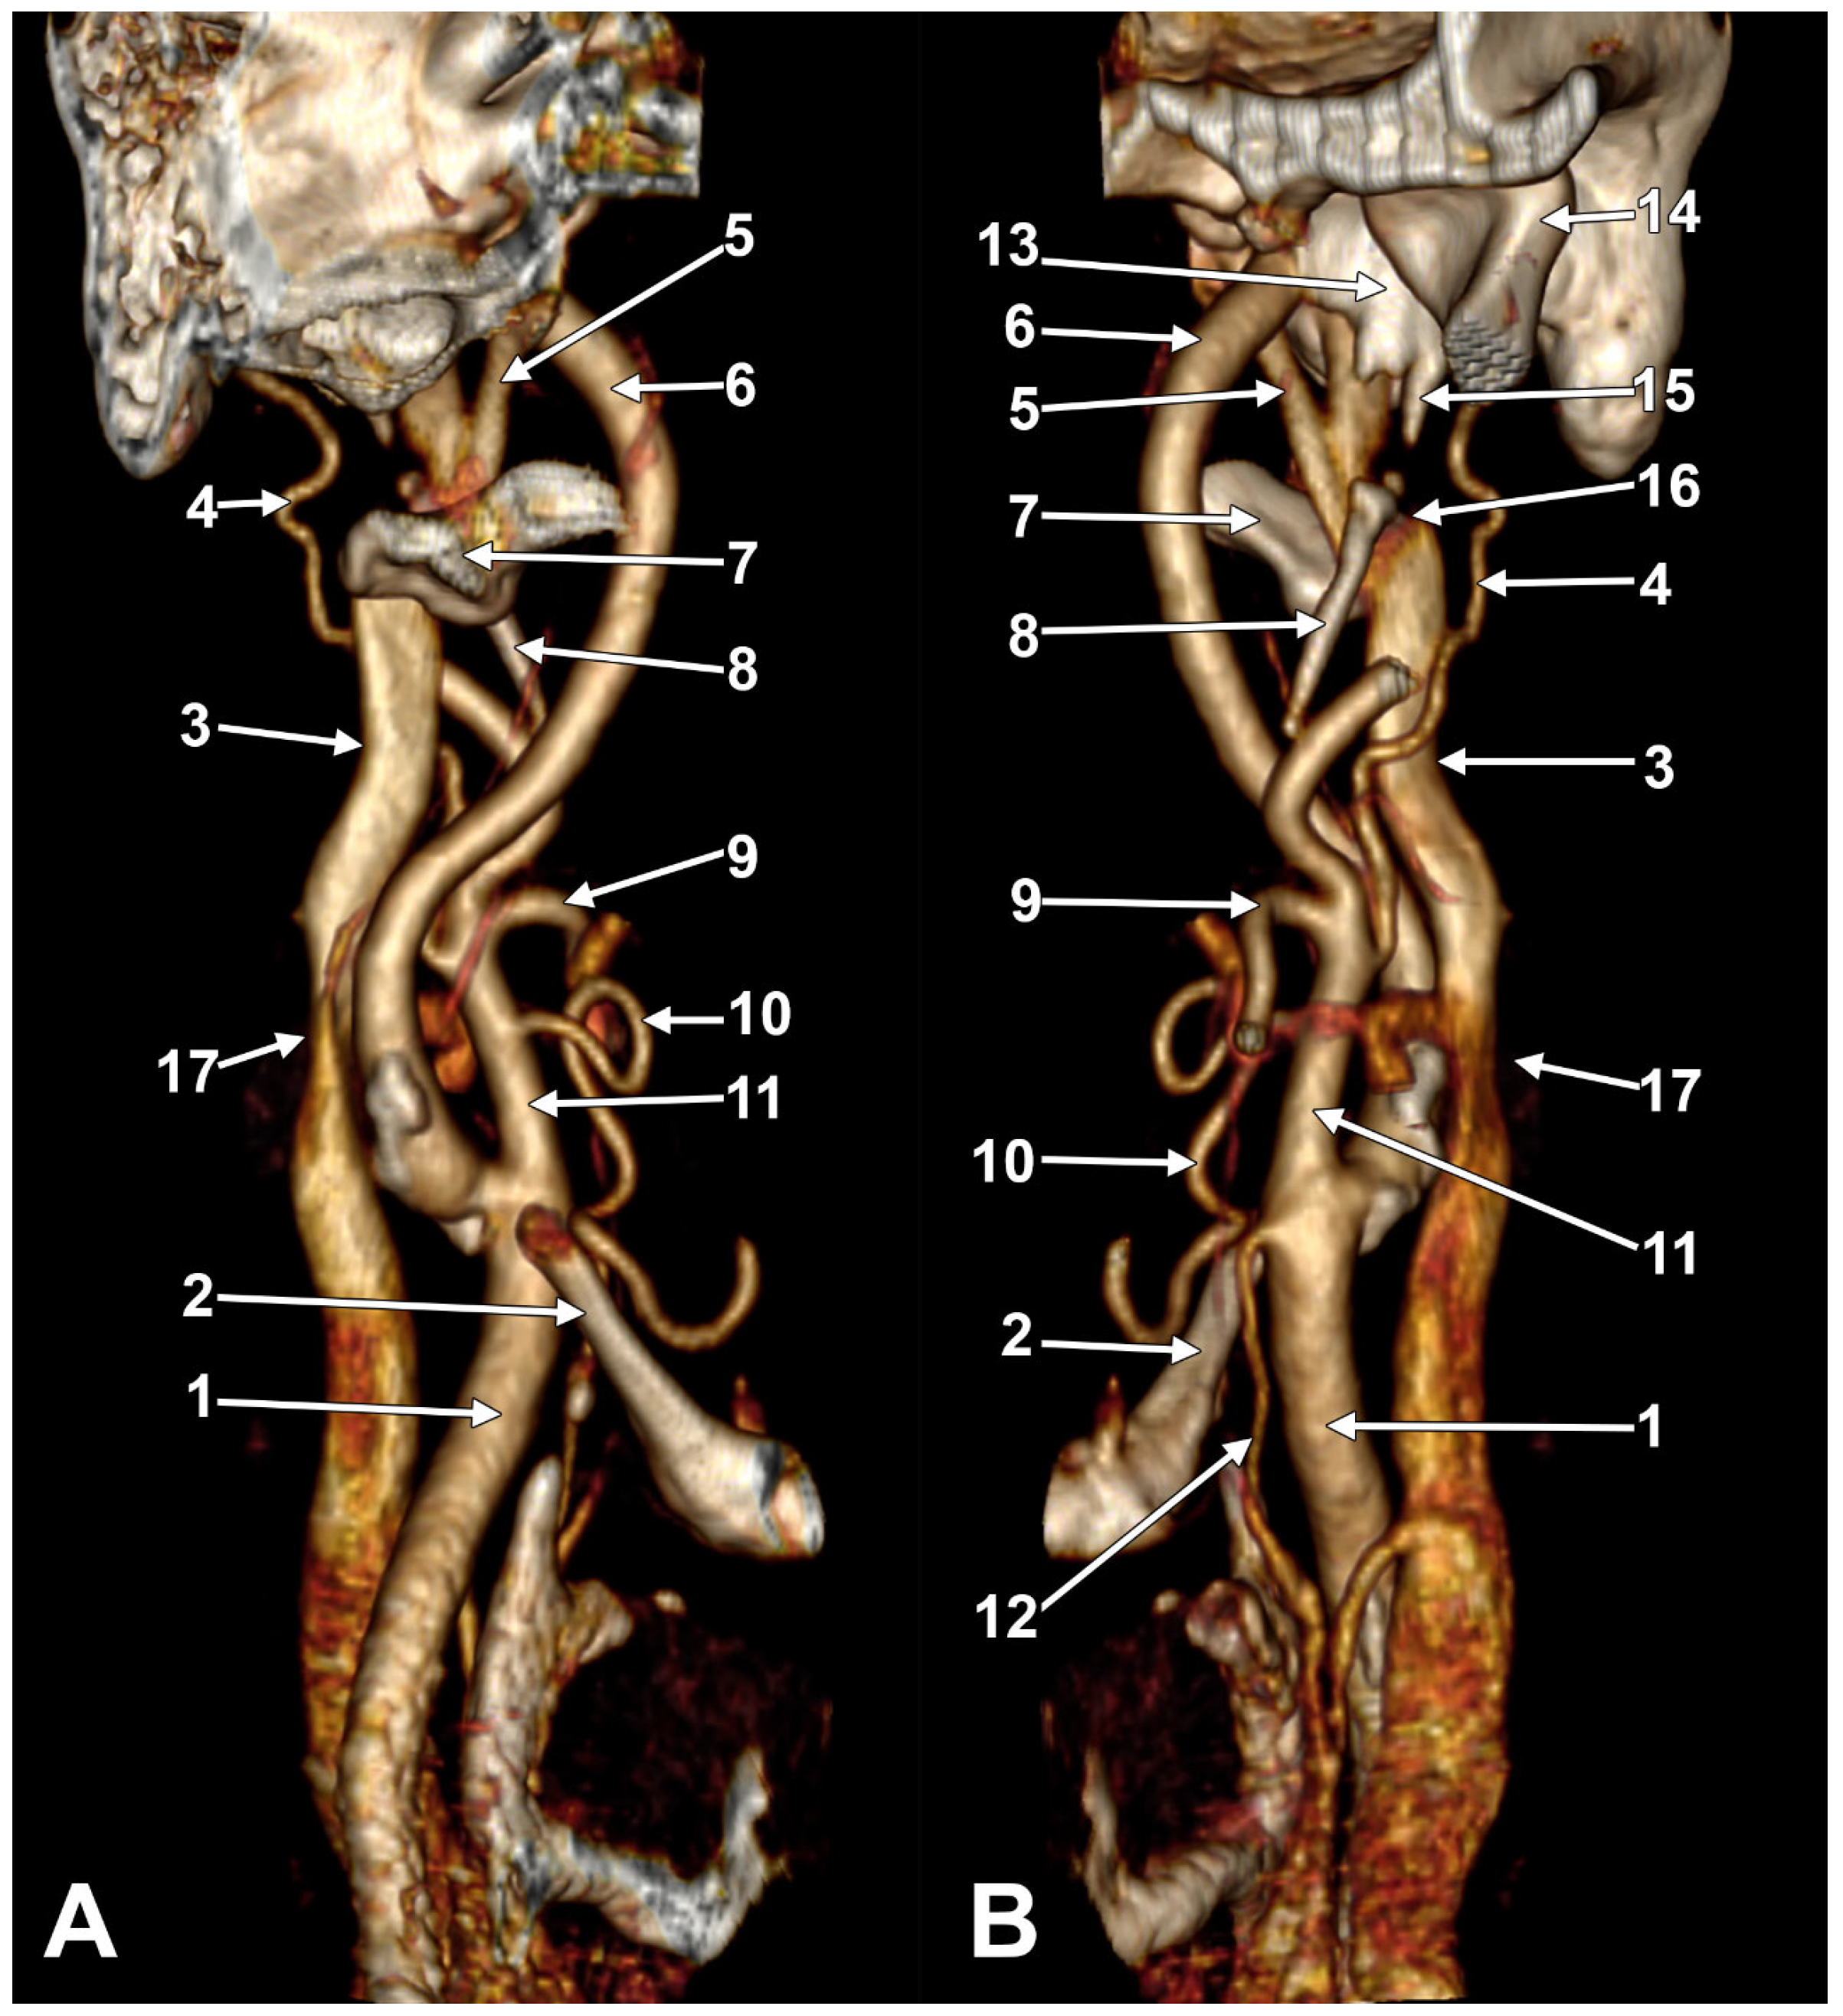

We present here a case with bilateral long IPSs (Figure 7 and Figure 8). The novelty lies in the fact that both the long IPS and the IJV were pinched within the C1/SP nutcracker. This is because, on the one hand, the stenosis of the IJV determines different neurological deficits, discussed elsewhere in this paper, and, on the other hand, a compressed IPS could not be of use as an endovascular passage when it is compressed into a nutcracker. Specific documentation of IPS compression between the SP and atlas appears to be either very rare in the literature or potentially underreported. During an anatomical study of the archived angioCT file of a 63-year-old male case, bilateral long IPSs were found. The right one was 1.25 cm long, and the left one was 5.15 cm long. The right one had a diameter of 0.2 cm. The opposite one had a diameter of 0.32 cm. The right IPS was joined beneath the jugular foramen by the lateral condylar vein. The left IPS descended antero-medially to the left IJV. Both these veins were applied and compressed on the anterior side of the transverse process of the atlas. The two veins continued anterolaterally to the transverse process of the axis, and at 0.41 cm below that process, the IPS ended into the IJV. On both sides, the ICAs crossed anteriorly to the IPSs to enter the carotid canals. Therefore, the anatomic route of the IPS, the long IPS-to-IJV confluence site, and the diameter of the IPS are relevant in clinical procedures, such as cavernous sinus sampling, which requires catheterisation of both IPSs. Knowledge of the venous anatomy, including variants of the IPS and its branches, is crucial for the diagnosis and treatment of parasellar lesions.